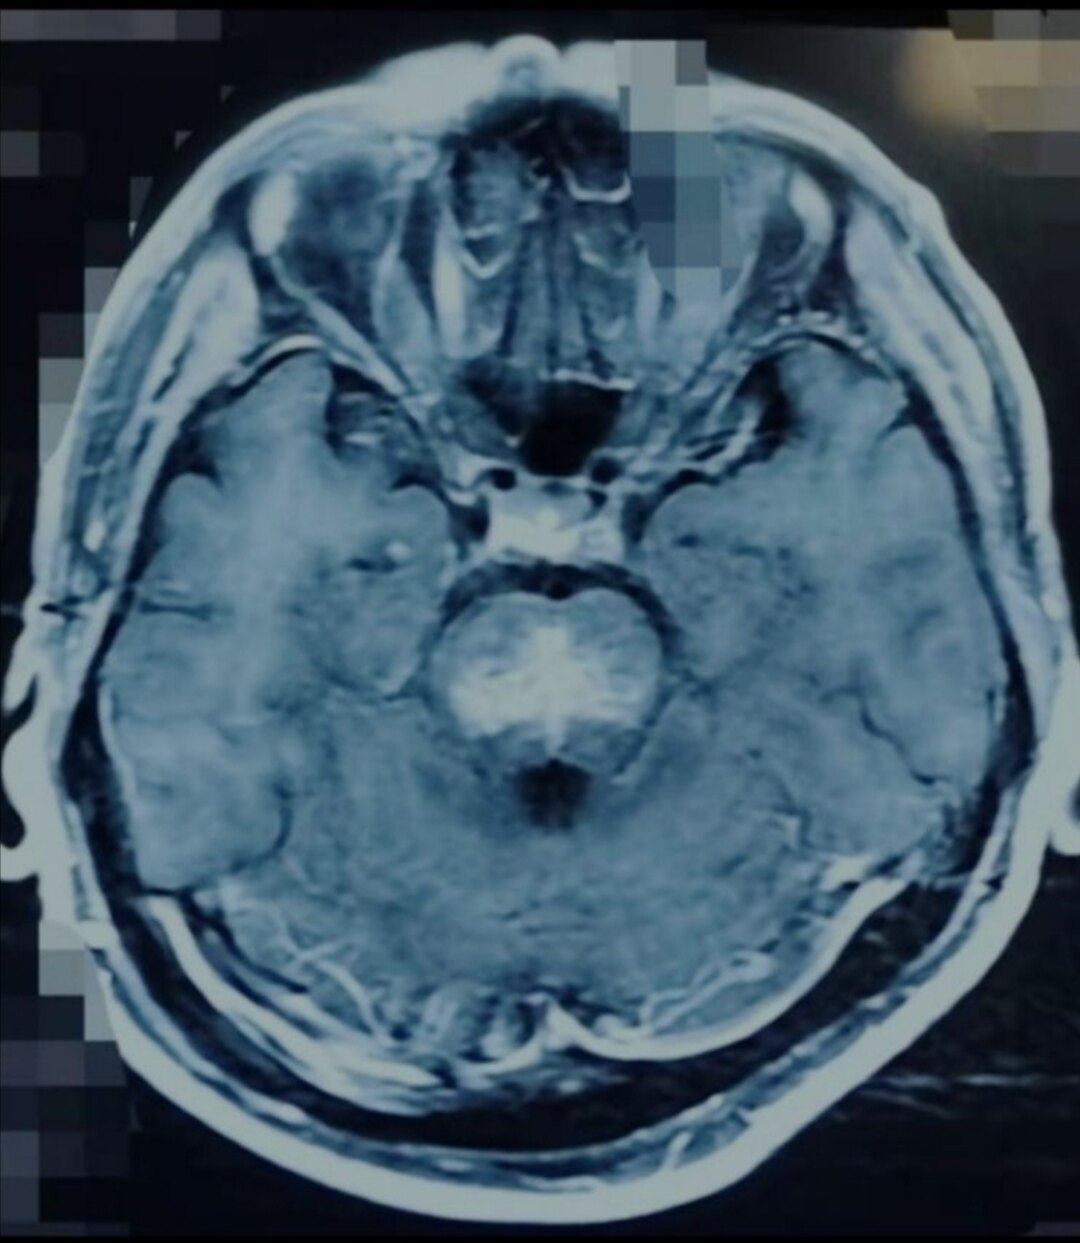

脑干胶质瘤